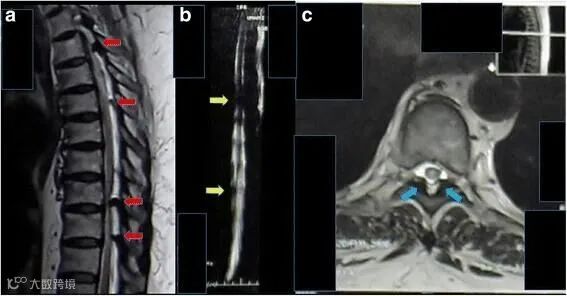

2017年海外报道一例62岁的印尼籍妇女,被诊断为胸部截瘫、慢性肾功能衰竭、糖尿病,长期肾脏受累,慢性肾功能衰竭2年,肌酐水平为11mg/dL,无小便。

采用间充质干细胞移植方案治疗。鞘内注射1.6×107个间充质干细胞,静脉注射1.6×107个间充质干细胞。

△ 患者胸部磁共振成像显示,脊髓受到多处压迫

鞘内注射和静脉注射后三周后,患者可以移动脚趾,肾功能得到改善。肌酐水平降至9 mg/dL。8个月后,患者可以抬起腿,肌酐水平是2mg/dL,小便恢复正常。